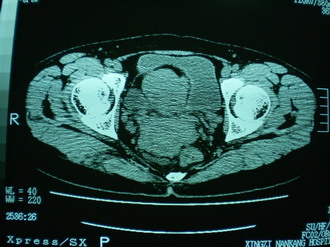

子宫增大,内可见类三角形低密度区,子宫后方可见类圆形团块状影,内部密度不均匀,可见靶样结构,结合病史考虑1子宫后方宫外孕(宫内假孕囊形成)2子宫肌瘤合并妊娠

子宫明显前倾,增大,宫颈增大呈分叶状。子宫直肠窝见不规则形水样低密度。(膀胱胀尿不理想)

考虑:1、宫颈部占位;

2、子宫直肠窝少量积液(盆腔炎所致)。

考虑:1、宫颈部占位(宫颈癌?);

2、子宫直肠窝少量积液。

1、前曲子宫,2、宫颈部占位?3、盆腔及右输卵管积液?宫内积血?4、左侧卵巢囊肿。